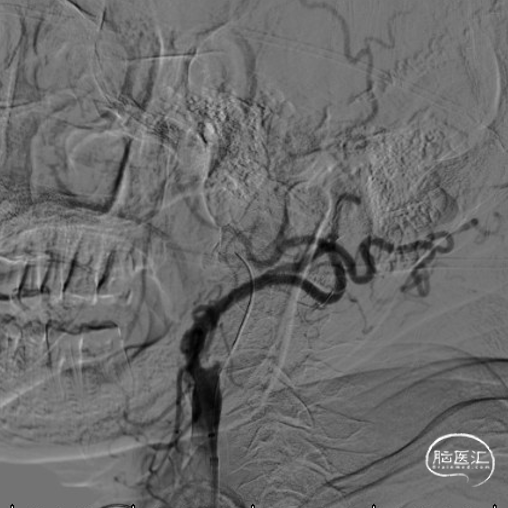

头颈部CTA

DSA

造影,颈内动脉未见血栓,颅内动脉较前未见明显减少,无明显血栓逃逸。

复查造影支架成形良好,颅内较前无明显改变,未发现血管减少影像,供血较前明显改善。